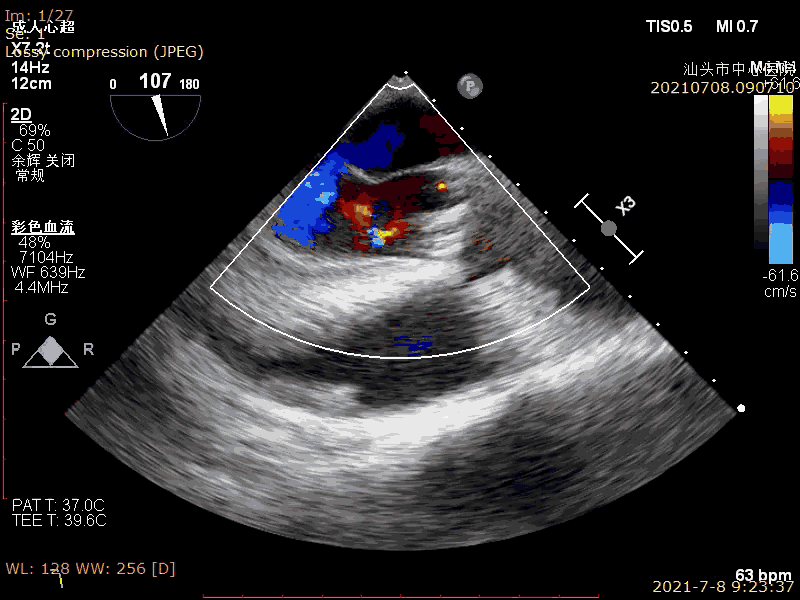

术前超声

超声示:

LVEF:37%

疑似低流量低压差病人

中-重度主动脉瓣狭窄并轻度反流